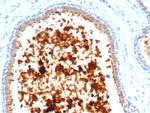

Antibodies that detect Mammaglobin can be used in several scientific applications, including Immunohistochemistry, Peptide array, Western Blot, Immunocytochemistry and ELISA. These antibodies target Mammaglobin in Human samples. Our Mammaglobin recombinant monoclonal,... Antibodies that detect Mammaglobin can be used in several scientific applications, including Immunohistochemistry, Peptide array, Western Blot, Immunocytochemistry and ELISA. These antibodies target Mammaglobin in Human samples. Our Mammaglobin recombinant monoclonal, monoclonal and polyclonal antibodies are developed in... Antibodies that detect Mammaglobin can be used in several scientific applications, including Immunohistochemistry, Peptide array, Western Blot, Immunocytochemistry and ELISA. These antibodies target Mammaglobin in Human samples. Our Mammaglobin recombinant monoclonal, monoclonal and polyclonal antibodies are developed in Rabbit and Mouse. Find the Mammaglobin antibody that fits your needs. Choose from 1 of 27 Mammaglobin antibodies, which have been validated in experiments with 79 images featured in our data gallery.

Antibodies that detect Mammaglobin can be used in several scientific applications, including Immunohistochemistry, Peptide array, Western Blot, Immunocytochemistry and ELISA. These antibodies target Mammaglobin in Human samples. Our Mammaglobin recombinant monoclonal, monoclonal and polyclonal antibodies are developed in Rabbit and Mouse. Find the Mammaglobin antibody that fits your needs. Choose from 1 of 27 Mammaglobin antibodies, which have been validated in experiments with 79 images featured in our data gallery.

Current literature indicates that mammaglobin, as measured by the ELISA, holds significant promise for breast cancer screening with the realistic potential to impact management of this disease.